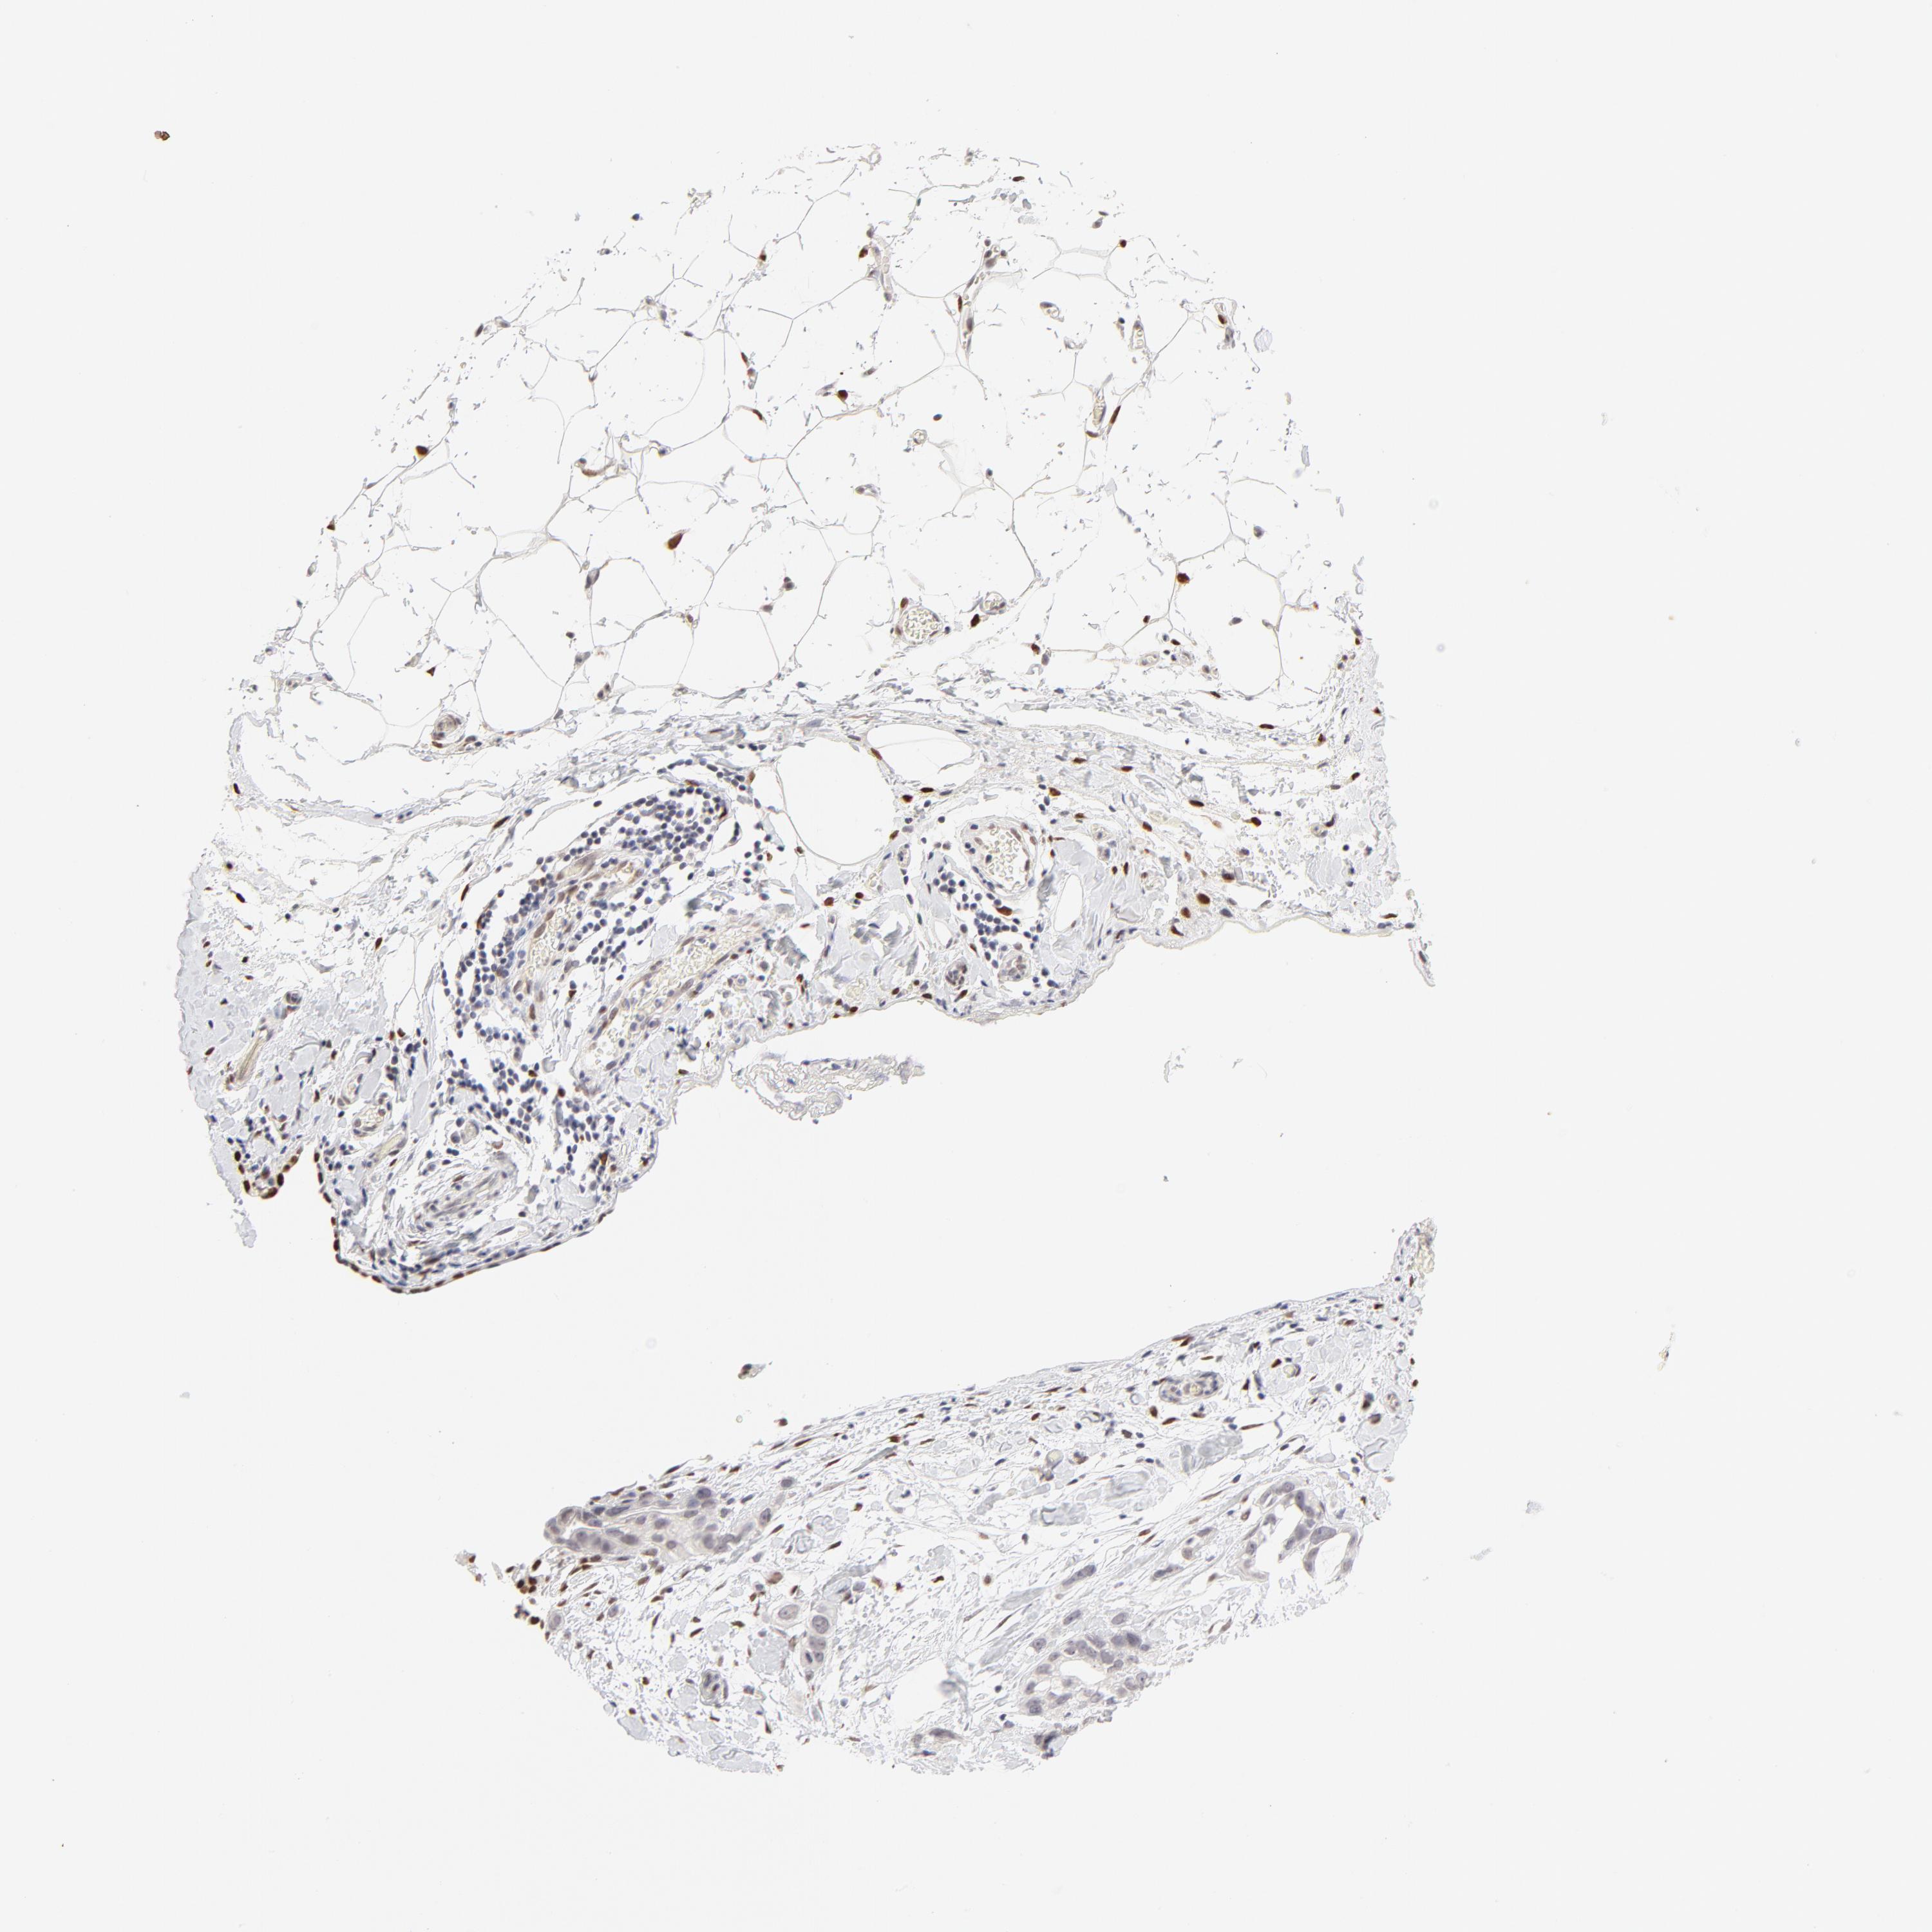

STOMACH CANCER - Protein expressioni

A mouse-over function shows sample information and annotation data. Click on an image to view it in a full screen mode. Samples can be filtered based on level of antibody staining by selecting one or several of the following categories: high, medium, low and not detected. The assay and annotation is described here.

Note that samples used for immunohistochemistry by the Human Protein Atlas do not correspond to samples in the TCGA dataset.

Antibody stainingi

Antibody staining in the annotated cell types in the current human tissue is reported as not detected, low, medium, or high, based on conventional immunohistochemistry profiling in selected tissues. This score is based on the combination of the staining intensity and fraction of stained cells.

Each image is clickable and will lead to virtual microscopy that enables deeper exploration of all samples and also displays staining intensity scores, fraction scores and subcellular localization as well as patient and tissue information for each sample.

Antibody HPA003505

Antibody HPA003881

Antibody CAB018768

Staining

Location

Nuclear

Cytoplasmic/membranous

Cytoplasmic/membranous,nuclear

None

Adenocarcinoma, NOS